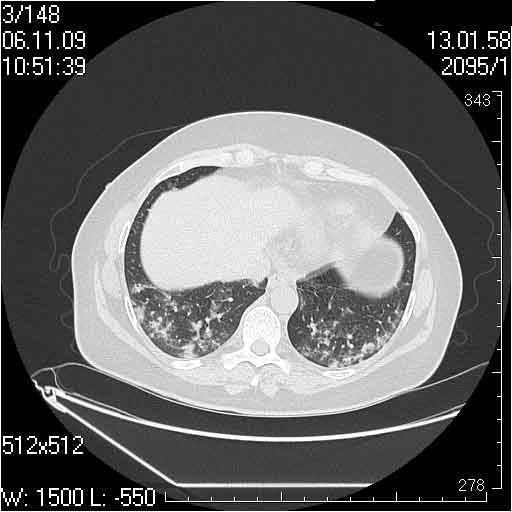

Случай №2

Мужчина 54 лет

Случай 2: картина патологических изменения довольно типична: GGOs & thickened interlobular septas = "crazy paving" sign. Наличие плотностей по типу матового стекла в сочетании с утолщением междолевых перегородок, даёт признак булыжной мостовой; на первом месте будет стоят диагноз альвеолярных протеиноз.